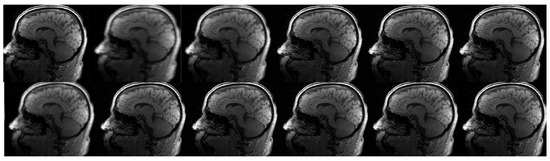

The acquired findings as depicted in Figure 8 and Figure 10, Figure 11 and Figure 12 demonstrate an enhancement in both the resolution and quality. The utilization of advanced methods for identifying potentially malignant or pre-cancerous anomalies led to improved resolution and legibility, hence enhancing the ability to detect such anomalies. Moreover, the achievements were validated by employing PSNR measures [50], which accurately evaluate the quality of medical images. This study involved an evaluation of the author’s methods in comparison to several advanced super-resolution image reconstruction algorithms. The current study focused on the reconstruction of an image using a regular sampling scheme, without the application of motion correction and SRR (1). To accomplish this, the reconstruction process involved the utilization of the B-spline curve (2) and Yang’s method [50] (3). Additionally, Lim’s method (4), Zhang’s procedure (5), Zhang’s second algorithm (6) (7), and Liu et al.’s [53] procedure (8) were employed. Lim’s method is referenced as [20], Zhang’s procedure as [51], and Zhang’s second algorithm as [18]. Furthermore, the reconstruction procedure utilized Guerreiro’s methodology [54] (9), Pham et al.’s approach [55] (10), and Shi’s method [17] (11) mentioned in the citation [20], as well as the author’s own method (12).

Figure 10. The results of the second phase of the clinical brain imaging trial. The current study focuses on the reconstruction of an image using various techniques. In the first row, the regular sampling scheme is utilized without motion correction and SRR applied (1) (PSNR = 21.26 dB). The reconstruction process involves the use of the B-spline curve (2) (PSNR = 23.29 dB), Yang’s method [50] (3) (PSNR = 26.41 dB), Lim’s method (4) (PSNR = 29.22 dB) as referenced in [20], Zhang’s procedure (5) (PSNR = 28.71 dB) as referenced in [51], and Zhang’s second algorithm (6) as referenced in [43] (PSNR = 29.89 dB). In the second row, Mahapatra’s method [52] (7) (PSNR = 29.14 dB) and Wang et al.’s [53] procedure (8) (PSNR = 30.11 dB) are employed. Furthermore, the reconstruction procedure utilized Guerreiro’s approach [54] (9) (PSNR = 29.77 dB), Pham et al.’s method [55] (10) (PSNR = 23.48 dB), Shi’s method [17] (11) (12) (PSNR = 30.01 dB), as well as the author’s method (12) (PSNR = 32.61 dB). Furthermore, in order to achieve super-resolution, a suggested sampling strategy and motion correction techniques were employed. The aforementioned procedures were implemented without the inclusion of supplementary data. The compression ratio is 50%.

Figure 11. The results of the second phase of the clinical brain imaging trial. This study utilizes the fastMRI test dataset [57]. The current study focuses on the reconstruction of an image using various techniques. In the first row, the regular sampling scheme is utilized without motion correction and with SRR applied (1) (PSNR = 20.11 dB). The reconstruction process involves the use of the B-spline curve (2) (PSNR = 23.31 dB), Yang’s method [50] (3) (PSNR = 27.01 dB), Lim’s method (4) (PSNR = 29.12 dB) as referenced in [20], Zhang’s procedure (5) (PSNR = 28.66 dB) as referenced in [51], and Zhang’s second algorithm (6) (PSNR = 29.71 dB) as referenced in [43]. In the second row, Mahapatra’s method [52] (7) (PSNR = 29.32 dB) and Wang et al.’s [53] procedure (8) (PSNR = 30.62 dB) are employed. Furthermore, the reconstruction procedure utilizes Guerreiro’s approach [54] (9) (PSNR = 28.82 dB), Pham et al.’s method [55] (10) (PSNR = 26.58 dB), Shi’s method [17] (11) (PSNR = 31.22 dB), and the author’s method (12) [20]. Furthermore, in order to achieve super-resolution, a suggested sampling strategy and motion correction techniques are employed. The aforementioned procedures are implemented without the inclusion of supplementary data. The compression ratio is 50%.

Figure 12. The results of the second phase of the clinical brain imaging trial. This study utilizes the fastMRI test dataset [57]. The current study focuses on the reconstruction of an image using various techniques. In the first row, the regular sampling scheme is utilized without motion correction and with SRR applied (1) (PSNR = 22.89 dB). The reconstruction process involves the use of the B-spline curve (2) (PSNR = 23.22 dB), Yang’s method [50] (3) (PSNR = 26.30 dB), Lim’s method (4) (PSNR = 29.71 dB) as referenced in [20], Zhang’s procedure (5) (PSNR = 28.54 dB) as referenced in [51], and Zhang’s second algorithm (6) (PSNR = 29.77 dB) as referenced in [43]. In the second row, Mahapatra’s method [52] (7) (PSNR = 29.23 dB) and Wang et al.’s [53] procedure (8) (PSNR = 30.21 dB) are employed. Furthermore, the reconstruction procedure utilizes Guerreiro’s approach [54] (9) (PSNR = 30.77 dB), Pham et al.’s method [55] (10) (PSNR = 23.65 dB), Shi’s method [17] (11) (PSNR = 30.80 dB), and the author’s method (12) (PSNR = 34.02 dB) [20]. Furthermore, in order to achieve super-resolution, a suggested sampling strategy and motion correction techniques are employed. The aforementioned procedures are implemented without the inclusion of supplementary data. The compression ratio is 50%.